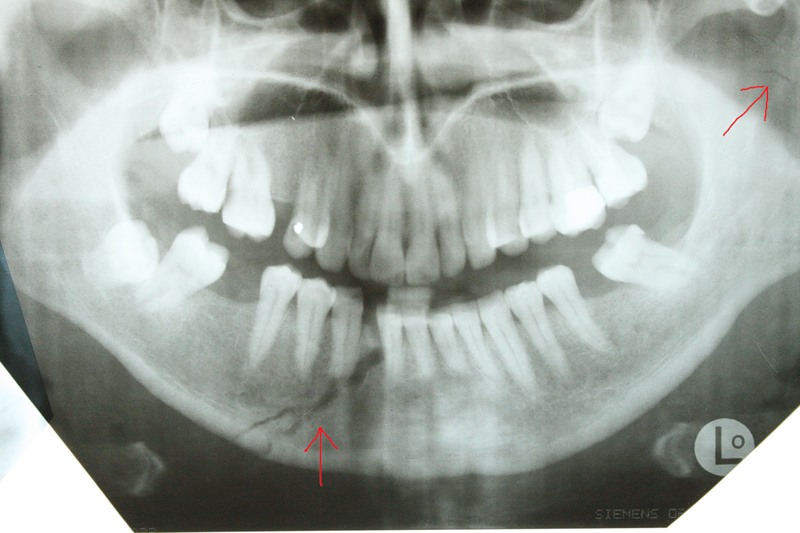

Симптомы и диагностика: Переломы челюсти могут проявляться не только болевыми ощущениями, но и нарушением прикуса, отеком, а также подвижностью зубов. Для диагностики часто используются рентгенографические исследования, такие как панорамная рентгенография или КТ, что позволяет точно определить место и характер перелома.

Фото

Переломы челюсти — серьезная травма, возникающая из-за ДТП, падений или спортивных инцидентов. Существуют различные типы переломов: нижней челюсти, суставного отростка и верхней челюсти. Каждый из них имеет свои особенности и требует индивидуального подхода к лечению. Например, переломы нижней челюсти могут быть открытыми или закрытыми, в зависимости от повреждений мягких тканей.